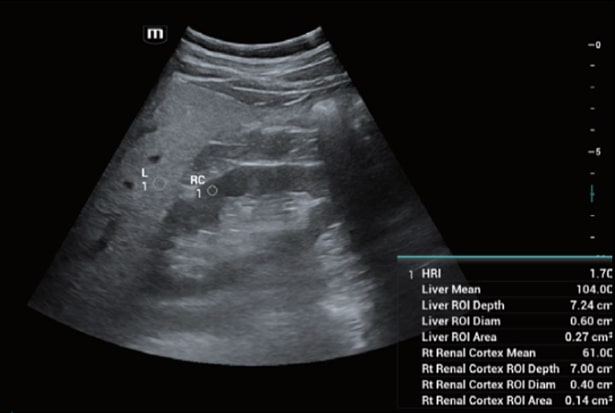

Функция Smart HRI автоматически определяет область печени и коркового слоя почек, устанавливает контрольные окна и рассчитывает коэффициент яркости ткани. Метод позволяет быстро и неинвазивно оценить степень стеатоза на основе гепаторенального индекса, снижая субъективность и экономя время врача.

Система определяет участки печени (L) и коркового слоя почки (RC), автоматически устанавливает области интереса и рассчитывает соотношение яркости тканей для количественной оценки степени стеатоза